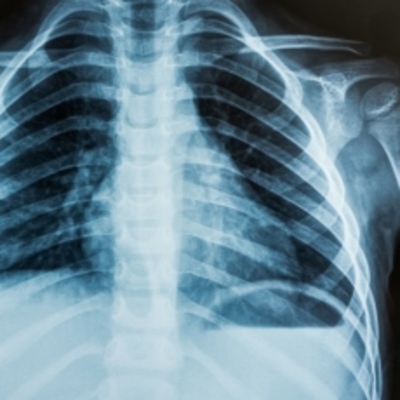

Descubrimiento de los rayos X (100 años antes) Vázquez Alamilla Karen Yessenia